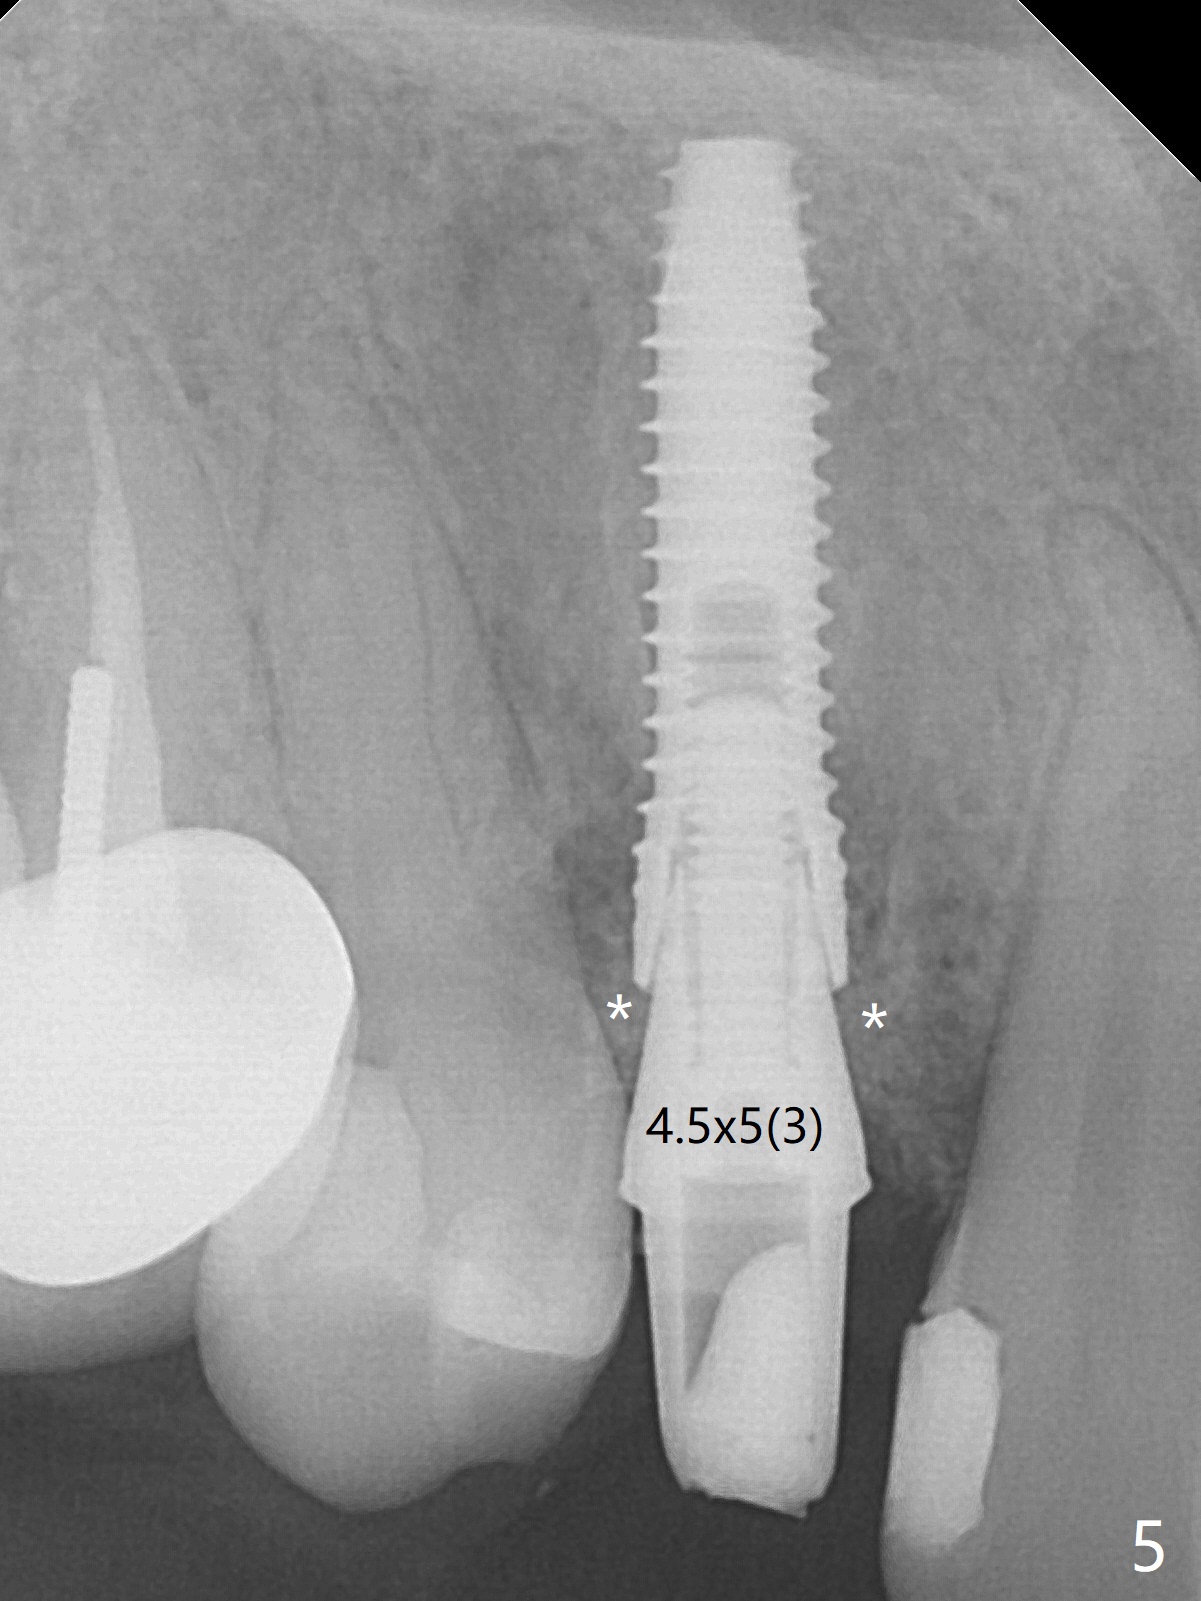

When the tooth #6 with loose crown and post (Fig.1) is extracted, there is no granulation tissue in the socket with the thin intact buccal plate. As planned, osteotomy is initiated in the mesio-palatal slope of the socket (Fig.2 red dashed line). After osteotomy for 3x20 mm (gingival level), a 3.8x15 mm dummy implant is placed partially (Fig.3 D). A final implant with the same dimension is placed with > 50 Ncm (Fig.4). Before and after placement of a 4.5x5(3) mm abutment, Vera graft is placed in the remaining socket space (mainly buccal, Fig.5 *). As routine, an immediate provisional is fabricated with occlusal clearance. The gingiva looks healthy around the provisional 1 week postop (Fig.6 P). Adjust and polish the mesioocclusal composite at #5 if necessary before impression. The bone graft appears to remain in place 4.5 months postop (Fig.7). A bevel buccal subgingival margin is placed prior to impression. The bone density around the coronal portion of the implant increases 9 months postop (4 months post cementation, Fig.8). There is no gingival erythema or edema around the implant crown at #6 ten months post cementation (Fig.6, as compared to preop condition and that of the neighboring crown (*)). Both the buccal and palatal plates are thin or absent 1 year 5 months post cementation (Fig.10,11, as compared to Fig.12 for the tooth #11 (thin buccal bone)). Socket shield should be done with a smaller implant.